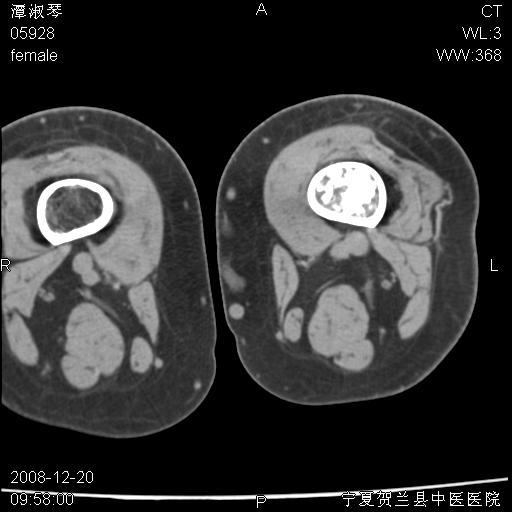

标题: CT17526:请各位看看是啥? [打印本页]

标题: CT17526:请各位看看是啥?

内生软骨瘤?骨梗死?

考虑内生软骨瘤可能性大

考虑-----骨梗死+退变

支持骨梗死,退行性骨关节病,膝关节积液.

考虑骨梗死可能性大

支持骨纤或内生软骨瘤或骨梗死,退行性骨关节病,膝关节积液.

骨梗死可能性大

左侧股骨下段骨瘤

左股骨下段骨梗死。双膝退变。

支持:内生软骨瘤或骨梗死!另:退行性骨关节病,膝关节积液。

支持骨纤或内生软骨瘤或骨梗死,退行性骨关节病,膝关节积液

支持骨梗死

左胫骨下端松质骨及髓腔内可见点片状高密度灶,骨皮质无明显膨胀及变薄。病变范围较长。支持骨梗死,退行性骨关节病,膝关节积液